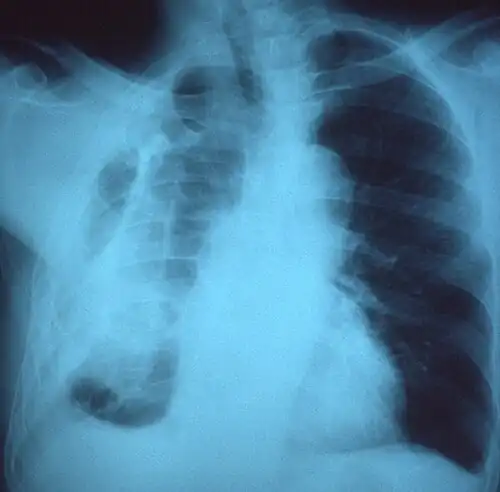

Фиброторакс, как правило, может быть диагностирован путем сбора истории болезни в сочетании с использованием соответствующих методов визуализации, таких как рентгенография грудной клетки или компьютерная томография (КТ). Эти методы визуализации могут обнаружить фиброторакс и утолщение плевры, которые окружают легкие. Присутствие утолщенной кожуры с кальцификацией или без нее являются общими признаками фиброторакса при визуализации. КТ помогает лучше чем рентген различать причину утолщение плевры: из-за избыточного отложения жира или истинного утолщения плевры.

Если фиброторакс тяжелый, утолщение может ограничить легкое на пораженной стороне, вызывая потерю объема легкого. Кроме того, средостение может быть физически смещено в сторону пораженной стороны. Уменьшение размера одной стороны грудной клетки (гемиторакса) при рентгенографии или компьютерной томографии грудной клетки предполагает хроническое рубцевание. Признаки основного заболевания, вызывающего фиброторакс, также иногда видны на рентгенограмме. КТ может показать признаки, подобные тем, которые видны на обычном рентгеновском снимке. Тестирование функции легких обычно демонстрирует результаты, согласующиеся с болезнью сжатия легких.